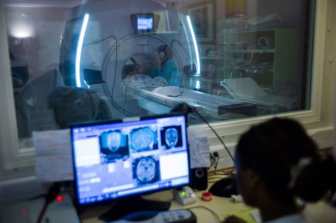

CT Scans

AHS says more MRI, CT scans being completed than before COVID-19 pandemicAHS says nearly 20,000 of the scans were performed in the first two weeks of September, compared to an average of 17,000 in 2018 and 2019.HealthOct 3, 2022

Some Alberta imaging procedures postponed due to global dye shortageAlberta Health Services said on Friday imaging procedures will only be deferred if it is clinically safe to do so.HealthJun 10, 2022

B.C. completes record-breaking number of MRI and CT scansThe annual scan progress report, released on Thursday, shows the province performed 296,211 MRIs in the 2021/22 fiscal year.HealthJun 9, 2022

St. Joe’s seeks to add CT scanner to its emergency department to reduce wait times, code zerosSt. Joseph's Healthcare is asking for help meeting its goal of bringing a CT scanner into the emergency department to reduce wait times and cut down on ambulance offloading delays.HealthDec 3, 2021

Edmonton doctors say long wait times for MRI and CT scans are getting worseAccording to the Edmonton Zone Medical Staff Association, the average wait for an MRI at the University of Alberta Hospital is now 375 days.HealthFeb 21, 2020

Federal health minister tells Saskatchewan to stop private MRIsThe federal health minister is asking the Saskatchewan government to "put an end" to the province's private-pay MRI services.HealthNov 28, 2016

CT scanner now operational at Leduc Community HospitalLeduc Community Hospital patients will now have access to specialized diagnostic technology with the addition of a new CT Scanner.HealthFeb 11, 2016

Alberta’s PET/CT scan delay extended up to 10 more daysAlberta patients waiting for PET/CT scans may have to wait even longer than expected due to a mechanical issue with a machine that produces material required to perform the scans.CanadaNov 2, 2015

Radiologist mistakes prompt Ontario hospitals to review 3,500 CT scans, mammogramsHealth officials are reviewing the results of 3,500 CT scans and mammograms at two hospitals in Mississauga, Ont., because of potential errors caused by a radiologist’s “performance issue.”CanadaSep 12, 2013